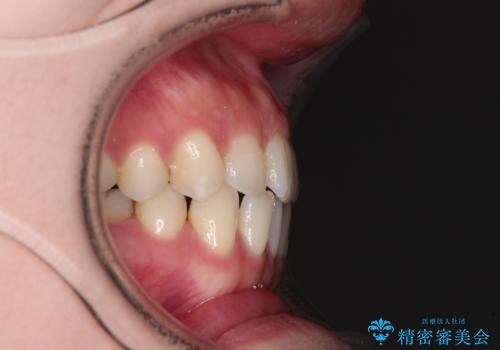

すきっ歯をインビザラインできれいな歯並びに改善

- 前歯の隙間を気にして来院された患者様です。

隙間や叢生の程度はそれほど著しいものではなかったので、インビザラインでもワイヤー矯正でも対応可能でしたが、極力目立たない装置を希望されたため、インビザラインにて矯正治療を行うこととしました。